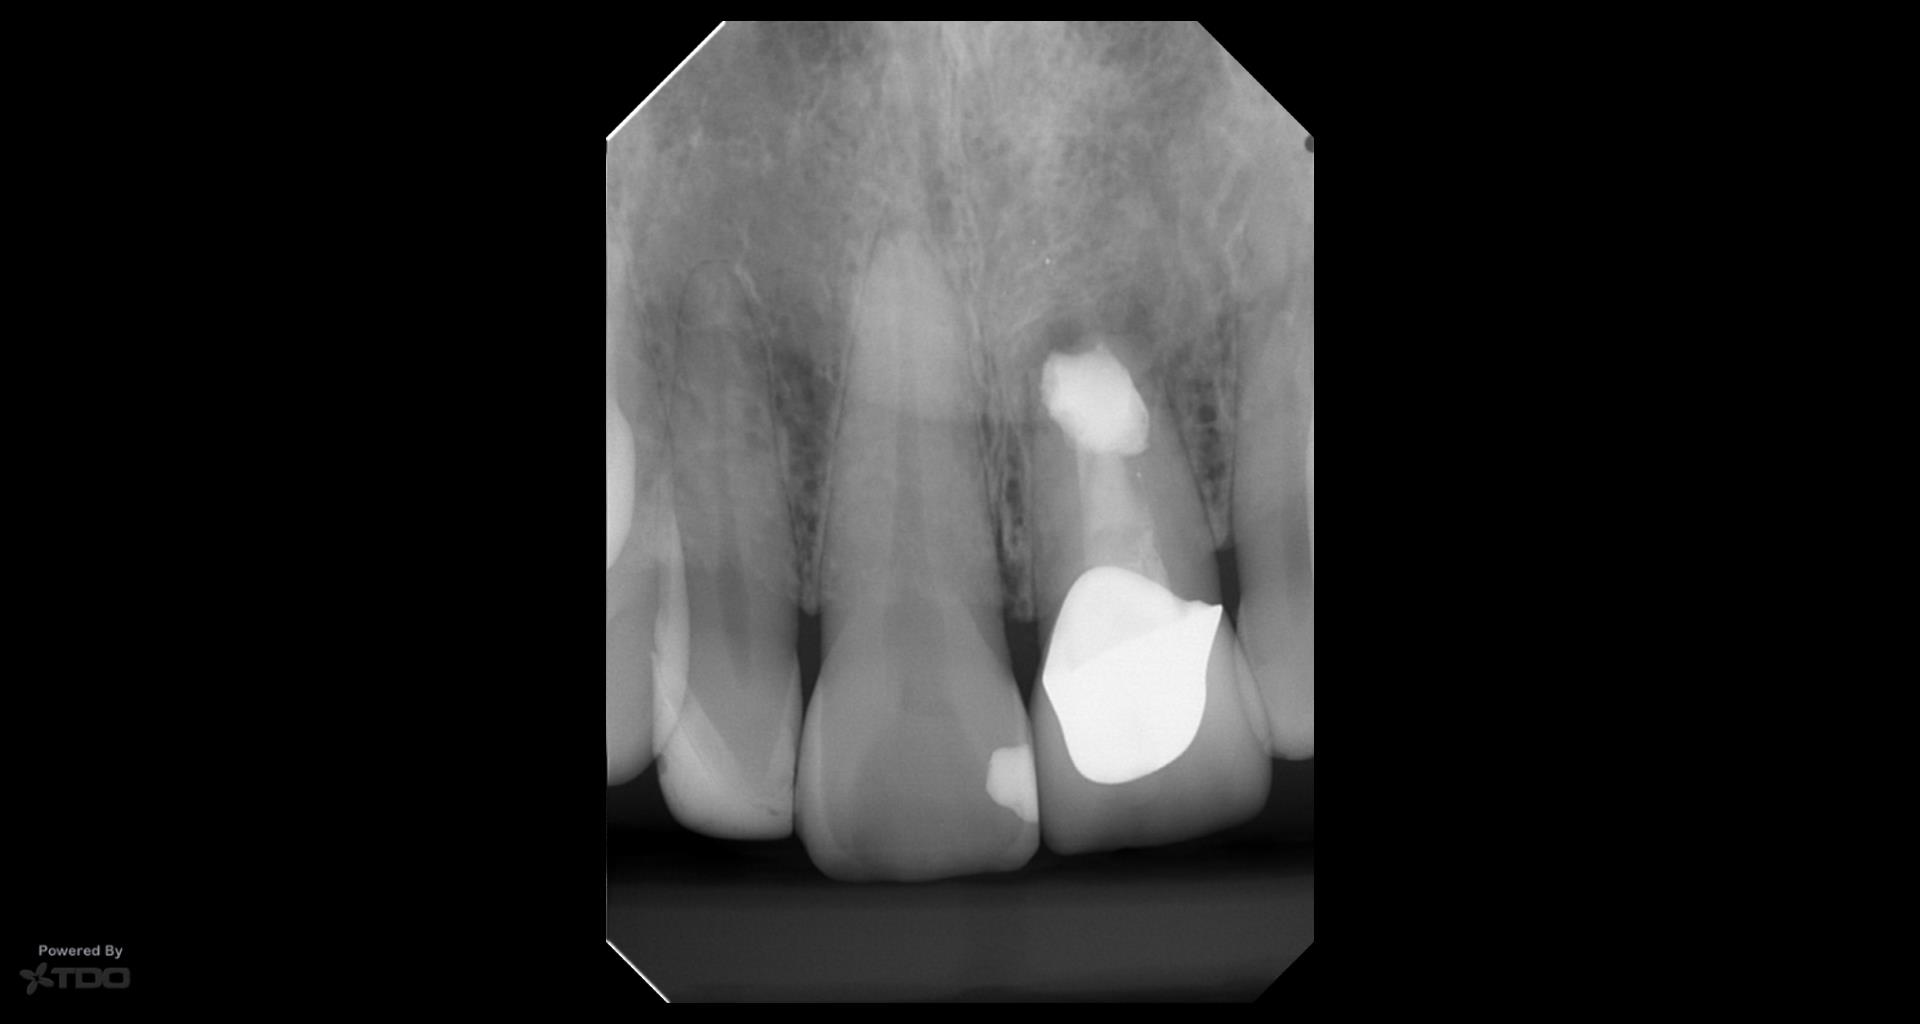

This was interesting because a root frac ture was seen where the prior apico was done. The MTAS was removed and Brassler putty used in this case. Will take a 1 yr CBCT and we will know more. Don’t usually get so much scar formation–so this was surprising…..